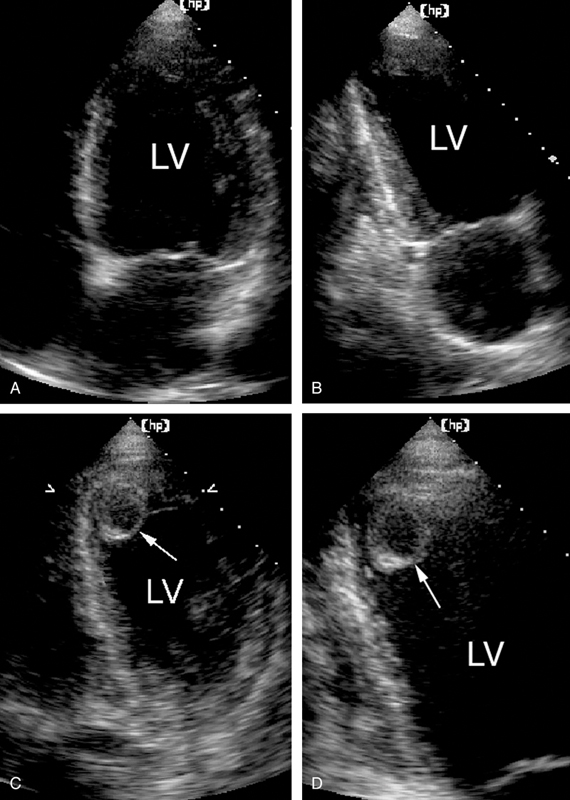

فحوصات تشخيصية لبعض امراض القلب والشرايين التاجية